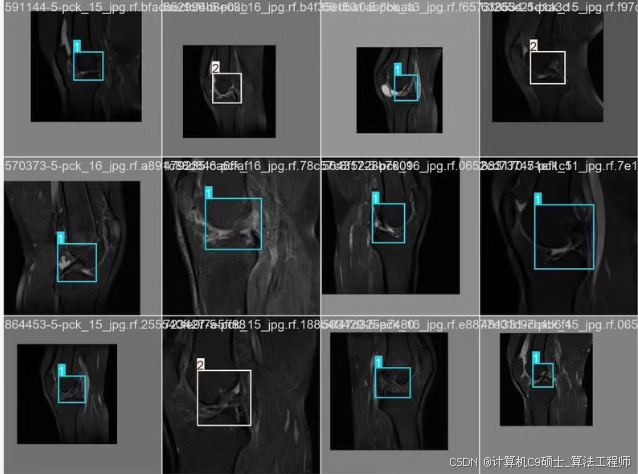

8. 可视化预测结果

使用以下Python代码来可视化模型的预测结果。

import torch

import cv2

import numpy as np

import matplotlib.pyplot as plt

# 加载模型

model = torch.hub.load('ultralytics/yolov5', 'custom', path='runs/detect/train/weights/best.pt')

# 读取图像

image_path = 'knee_injury_dataset/images/val/0001.jpg'

image = cv2.imread(image_path)

image = cv2.cvtColor(image, cv2.COLOR_BGR2RGB)

# 进行预测

results = model(image)

# 绘制预测结果

results.print()

results.show()